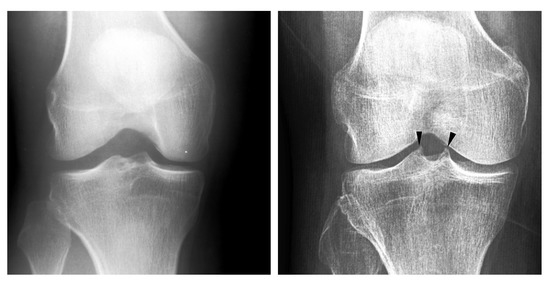

- Reiff, D.; Heron, C.; Stoker, D. Spiking of the tubercles of the intercondylar eminence of the tibial plateau in osteoarthritis. Br. J. Radiol. 1991, 64, 915–917. [Google Scholar] [CrossRef] [PubMed]

- Donnelly, S.; Hart, D.J.; Doyle, D.V.; Spector, T.D. Spiking of the tibial tubercles–a radiological feature of osteoarthritis? Ann. Rheum. Dis. 1996, 55, 105–108. [Google Scholar] [CrossRef] [PubMed]

- Unlu, Z.; Tarhan, S.; Goktan, C.; Tuzun, C. The correlation between magnetic resonance detected cartilage defects and spiking of tibial tubercles in osteoarthritis of the knee joint. Acta Medica Okayama 2006, 60, 207–214. [Google Scholar]

- Hayeri, M.R.; Shiehmorteza, M.; Trudell, D.J.; Heflin, T.; Resnick, D. Proximal tibial osteophytes and their relationship with the height of the tibial spines of the intercondylar eminence: Paleopathological study. Skelet. Radiol. 2010, 39, 877–881. [Google Scholar] [CrossRef] [PubMed]